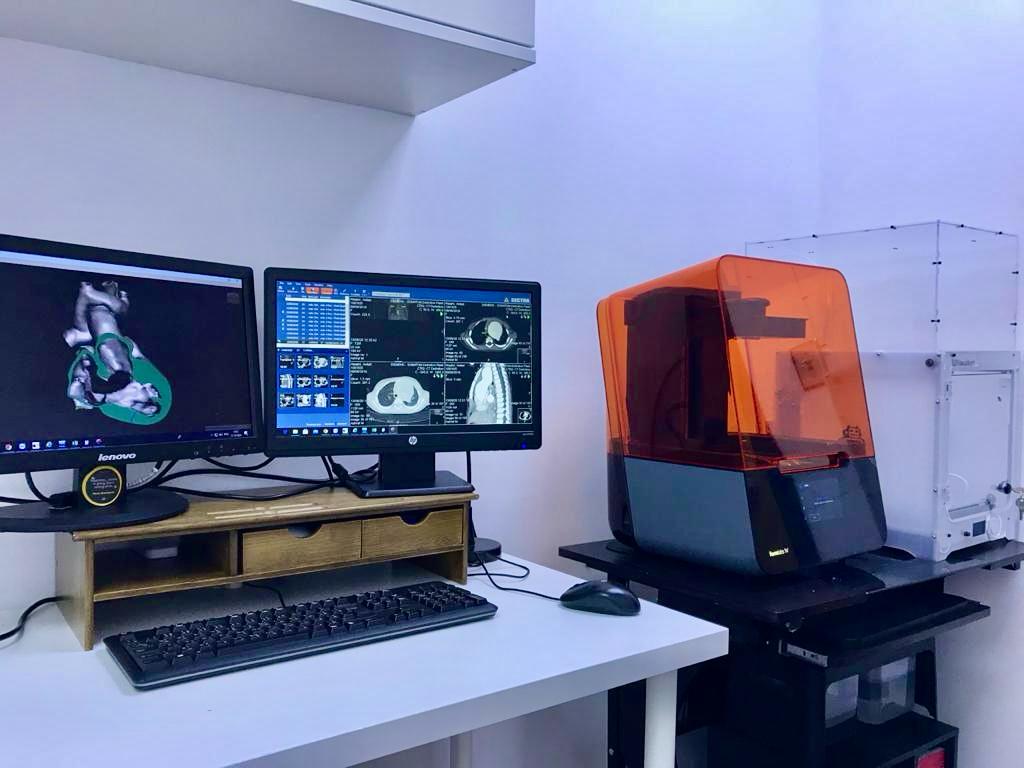

The technology follows a precise scientific process that begins with evaluating the patient’s condition using cardiac images obtained through ultrasound scans (echocardiography). In more complex cases, high-resolution computed tomography (CT) scans of the heart are used. These images are then processed using specialized software and transformed into tangible physical models that accurately reflect the true anatomy of the affected child’s heart.

It is worth noting that eligible cases are selected after careful scientific discussion within the specialized medical team to ensure the best possible care. The success of the 30 cases performed since 2020 reflects King Abdulaziz University Hospital’s commitment to keeping pace with global medical advancements